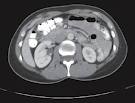

Ankle Abdomen

Computed Tomography (CT), also known as a CAT scan, is a sophisticated imaging technique that shows different levels of the anatomy. During CT imaging, the x-ray source rotates around the patient. Each rotation produces a single cross-sectional "slice", like the slices in a loaf of bread. These cross-sectional images are far superior in detail than standard x-rays and greatly enhance a physician's diagnosis.

CT is used to diagnose many conditions. In cancer detection, CT is used to scan for abnormal masses, showing the size and shape of the tumor, its precise location and whether it's solid or hollow. In addition, CT scans can provide valuable information in the detection of abscesses, strokes, head injuries and bleeding inside the skull.